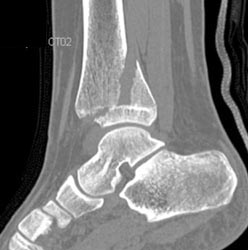

Tarsal Coalition